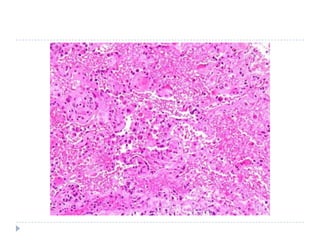

morfoloji

   Akut evrede akciğer ağır, sert, kırmızı ve çamurumsu

   Konjesyon, interstisyel ve intraalveoler ödem,

inflamasyon fibrin birikimi

   Hyalin membranlar

   Organizasyon evresinde tipII hücrelerde

proliferasyon

   Rezolüsyon nadir

   Ġntraalveoler fibrozis ile sonuçlanan fibrin

organizasyonu sık

   Ölümcül olgulara bronkopnömoni süperimpoze

morfoloji  Akut evrede akciğer ağır, sert, kırmızı ve çamurumsu  Konjesyon, interstisyel ve intraalveoler ödem, inflamasyon fibrin birikimi  Hyalin membranlar  Organizasyon evresinde tipII hücrelerde proliferasyon  Rezolüsyon nadir  Ġntraalveoler fibrozis ile sonuçlanan fibrin organizasyonu sık  Ölümcül olgulara bronkopnömoni süperimpoze